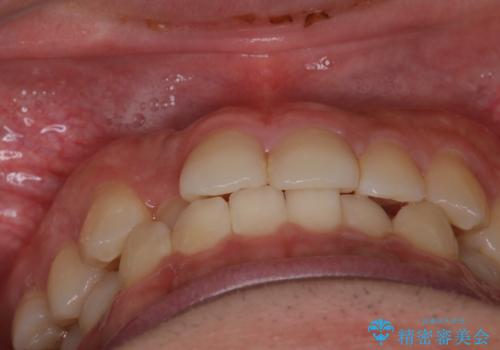

- 前歯のがたつきを主訴に来院されました。初診時、右上2番の口蓋側転位と右下7番の舌側傾斜が認められました。

インビザラインにてIPRと歯列弓拡大を行い、ゴム掛けで噛み合わせを改善する治療計画を立てました。